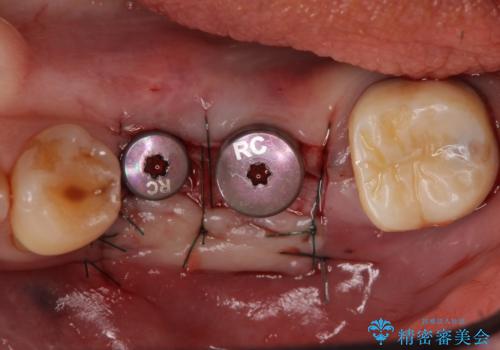

欠損部位である左下5、6番目にインプラントを埋入し、オールセラミッククラウンによる補綴を行いました。

- オールセラミッククラウン…¥100,000×3、仮歯…¥10,000×3、インプラント(ストローマン)…¥200,000×2、カスタムアバット…¥100,000×2、ファイバーコア…¥20,000、根管治療費別途費用は治療当時の料金となります

カスタムアバットメントについて

カスタムアバットメントは患者様それぞれの歯茎に合わせて製作されたオーダーメイドのアバットメントです。

既製のアバットメントに比べ適合がよく、高い清掃性を誇ります。